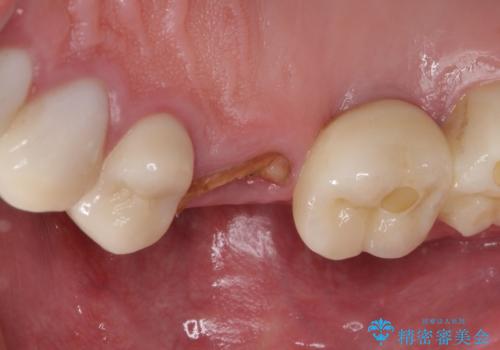

折れてしまった歯 インプラントによる補綴治療

- 咬合力により歯が割れてしまった方のインプラント治療です。

抜歯後4ヶ月ほど待ち、後方のインプラントと同一メーカーのインプラントを埋入することとしました。